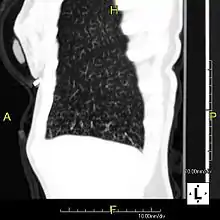

Sagittal reformatted CT image showing "tree in bud" appearance of impacted distal small airways in primary ciliary dyskinesia

Histopathologic studies have shown that the tree-in-bud pattern is caused by demarcation of the normally invisible branching course of the peripheral airways, which usually results from bronchioles being plugged or blocked with mucus, pus or fluid. In addition, dilated and thickened walls of the peripheral airways and peribronchitis can make the affected bronchioles more easily visible, as is seen in patients with cystic fibrosis.